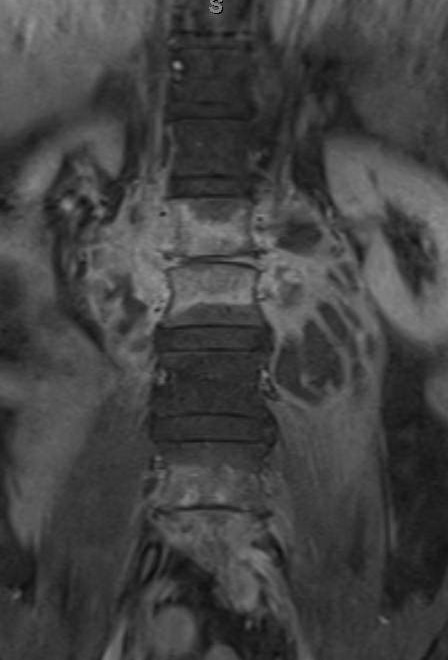

Case Presentation: A 62-year-old man presented with six months of progressive lower back pain. He noticed weight loss, sweats, and subjective fevers, but denied neurological symptoms or a other complaints. Patient lives in Texas, but travels to Mexico during winter. He denied tobacco abuse, intravenous drug use, incarceration or animal exposure. He reported eating unpasteurized cheese one year ago in Cuba and Mexico. Physical examination was positive for mild lumbar vertebral tenderness. Labs included an erythrocyte sedimentation rate of 64 mm/h and C-reactive protein of 4.4 mg /dL. White blood count was normal. Magnetic Resonance Imaging (MRI) of the lumbar spine showed infective lumbar spondylitis at L1-L2 and L4-L5 with extensive bilateral psoas abscesses. Blood and abscess aspirate cultures were obtained, and the patient was started on anti-tuberculosis medications given the classic MRI features of for tuberculosis. Abscess aspirate grew Brucella melitensis and anti-tuberculosis medications were changed to gentamycin and doxycycline

This case describes a patient with progressive back pain who was found to have lumbar spondylitis and bilateral psoas abscesses with features typical for tuberculous spondylitis. However, the culture grew Brucella melitensis. The patient did not improve despite two weeks of therapy. Abscesses were drained, and gentamycin was changed to rifampin. Afterwards, the patient‘s back pain improved and both doxycycline and rifampin were continued for four months after abscesses drainage.